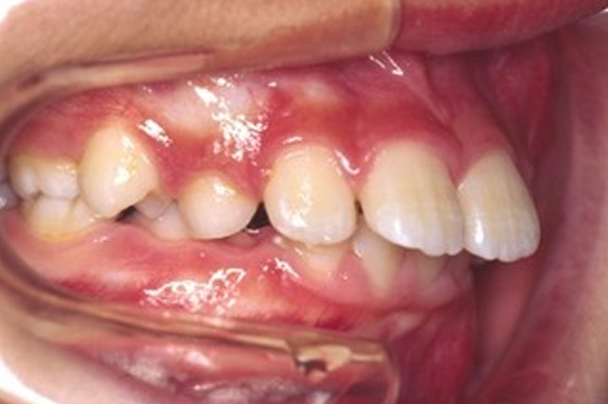

治療前

| 主訴 | 上の前歯が前に出ている。下あごが小さい。下の前歯が上あごに当たって痛い。 |

|---|---|

| 診断名 | 骨格性上顎前突(こっかくせいじょうがくぜんとつ)、過蓋咬合(かがいこうごう) |

| 治療に用いた装置 | アクチバトール |

上の前歯と下の前歯の間に1センチくらいの距離があり、口が閉じにくく見た目が気になるとのこと。また、前歯のかみ合わせがとても深いため、下の前歯と上あごの粘膜が接触しており、上あごの粘膜が炎症を起こして痛みのある状態でした。この患者さんは「出っ歯」と「過蓋咬合」の複合タイプのかみ合わせでした。出っ歯というと上の前歯が前方に出ている様子を想像しますが、この患者さんを検査したところ下あごが平均よりもかなり後ろに位置していることがわかりました。下あごの成長が弱い「骨格性上顎前突」という診断名でした。「アクチバトール」という取り外し可能な装置を使用することになりました。この装置を口の中に入れて口を閉じると、下あごを「前咬み」した状態になります。下あごを前咬みした状態を維持することで、成長期の患者さんであれば下あごの前方成長が促されます。また、この装置は前歯の深いかみ合わせ(過蓋咬合)を改善する働きもあります。この装置は睡眠時を中心に一日12時間使用するものですが、長時間使用した方が効果的であるため、毎日学校から帰宅したらすぐに装置を装着するようにお願いしました。